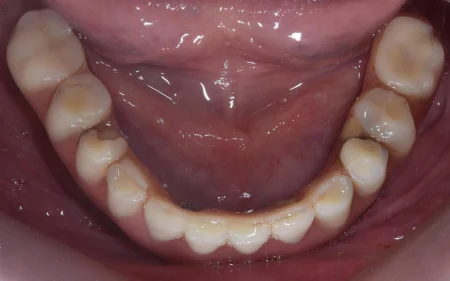

下のAll-on-4の写真です。

All-on-4は固定性のインプラントブリッジのため、ご自身で取り外しをすることなくお使いいただけます。

入れ歯と違って厚みも非常に薄いのが特徴です。 天然歯と遜色なくお使いいただけます。